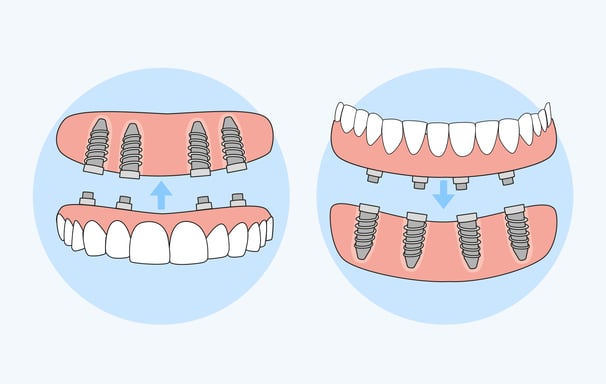

Son dentaduras que se apoyan sobre implantes dentales para mejorar su estabilidad y retención. Ofrecen una solución más segura y cómoda en comparación con las dentaduras tradicionales

Sobredentaduras

Combinan características de las prótesis fijas y removibles, generalmente ancladas a implantes dentales para mayor estabilidad. Son una solución intermedia que ofrece flexibilidad y soporte.

Colocación de prótesis híbridas